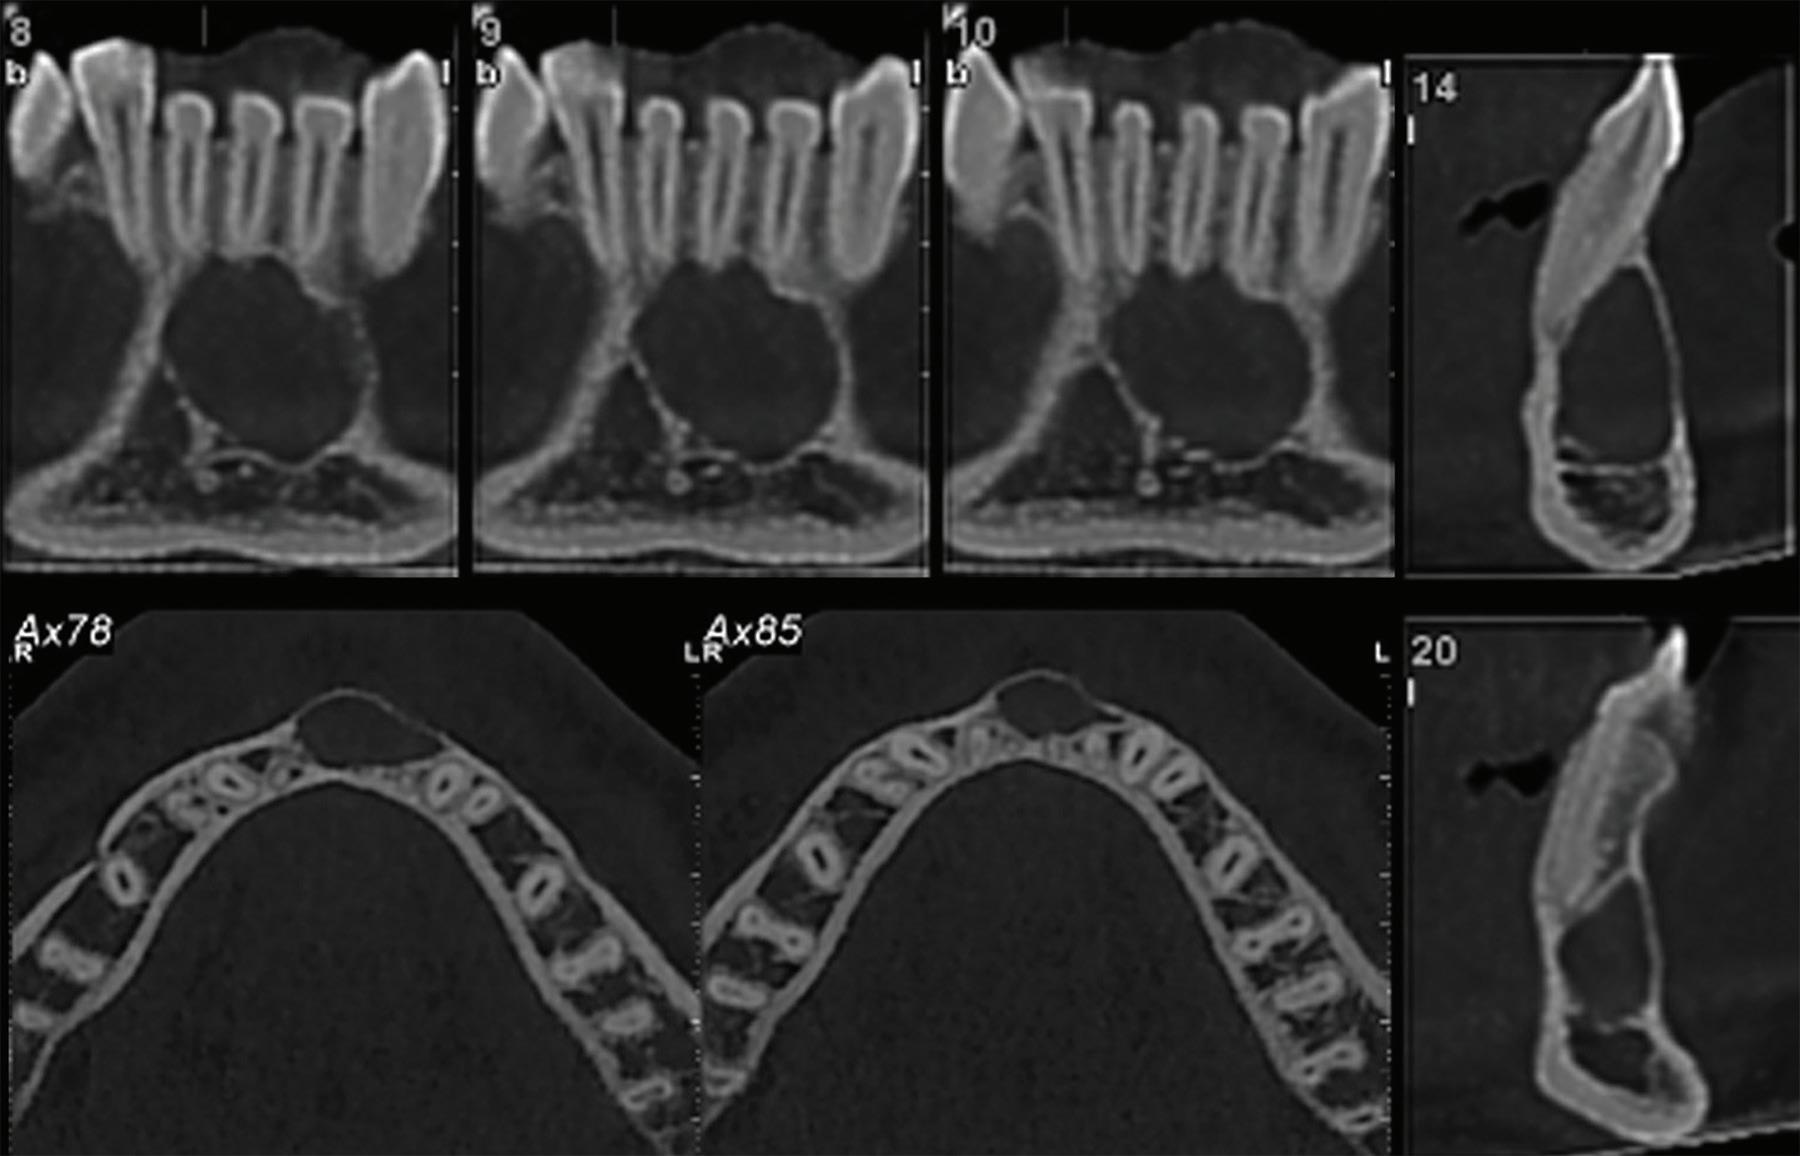

Root migration after coronectomy of impacted mandibular third molars: case reports

Gustavo Henrique de Souza Silva Enzo Balestrero

Jéssica Lemos Gulinelli

Pâmela Leticia dos Santos